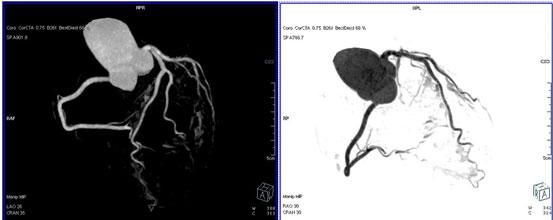

64排螺旋CT冠狀動脈血管成像:

1、簡單:無需經動脈插管,隻需象平時靜脈輸液一樣在肘靜脈内推注相對适量對比劑,然後行快速掃描即可完成整個檢查。

2、安全:64排螺旋CT冠狀動脈造影,對比劑用量較少,無需動脈插入導管,患者無需承擔麻醉及動脈插管等帶來并發症的危險。在冠狀動脈血管疾病的篩查、早期診斷、冠狀動脈成形術和搭橋術前、術後血管評價,冠狀動脈起源異常及心肌橋等方面極具優勢。

3、後處理功能豐富:西門子公司爲SOMATOM Definition AS+ 128層4D螺旋CT配備了功能強大的後處理工作站:MMWP(多産品工作站)和最新型的醫學影像IT工作平台,Syngo.via,智能,便捷。

CT冠脈血管成像: